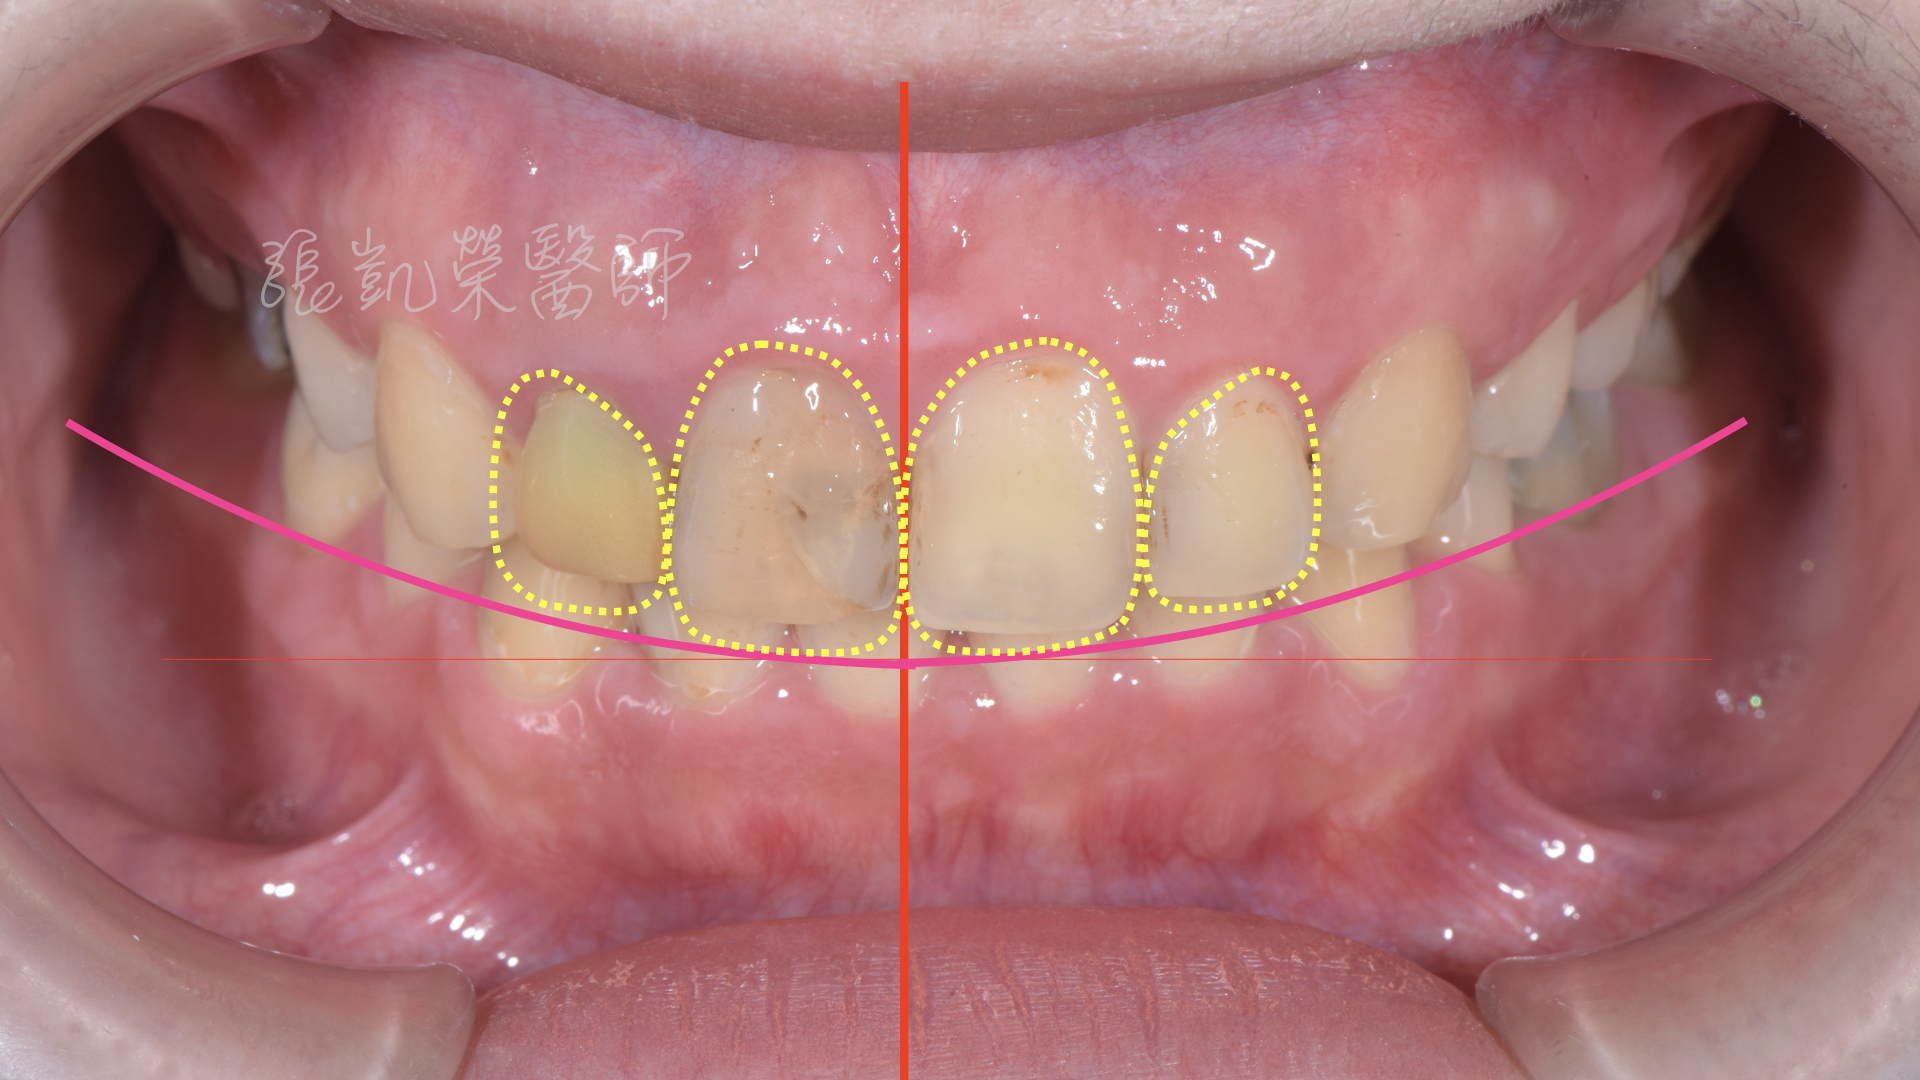

榮醫師檢查後發現,除了牙齒顏色外,還有中線偏斜、水平不齊、門牙大小不均、牙齦高低不齊等問題。

榮醫師建議先做牙齦整形術,將牙齦的位置調整齊,再用美白讓牙齒顏色亮白。

但除了做過根管治療的牙齒,牙齒較脆弱用全瓷冠修復外,其餘兩顆門牙為了減少傷害,用貼片修復,可以改善型態與大小,讓整體顏色、形態、中線水平做一併調整。